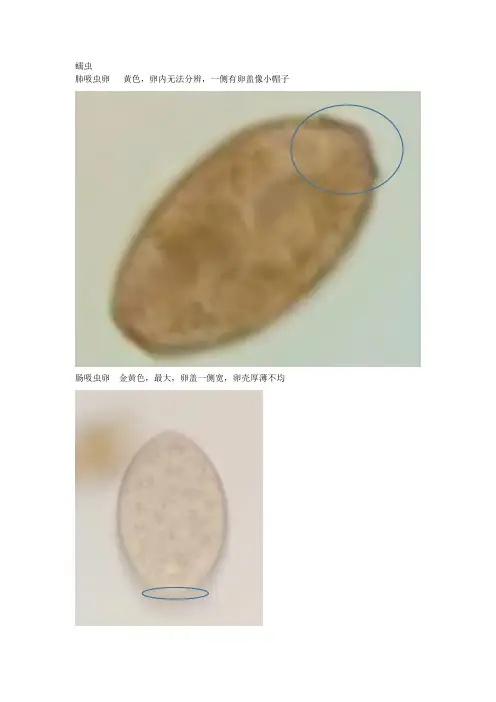

蠕虫肺吸虫卵黄色,卵内无法分辨,一侧有卵盖像小帽子肠吸虫卵金黄色,最大,卵盖一侧宽,卵壳厚薄不均肝吸虫卵卵盖、肩峰、小疣日本血吸虫尾蚴叉状尾血吸虫成虫形似线虫。